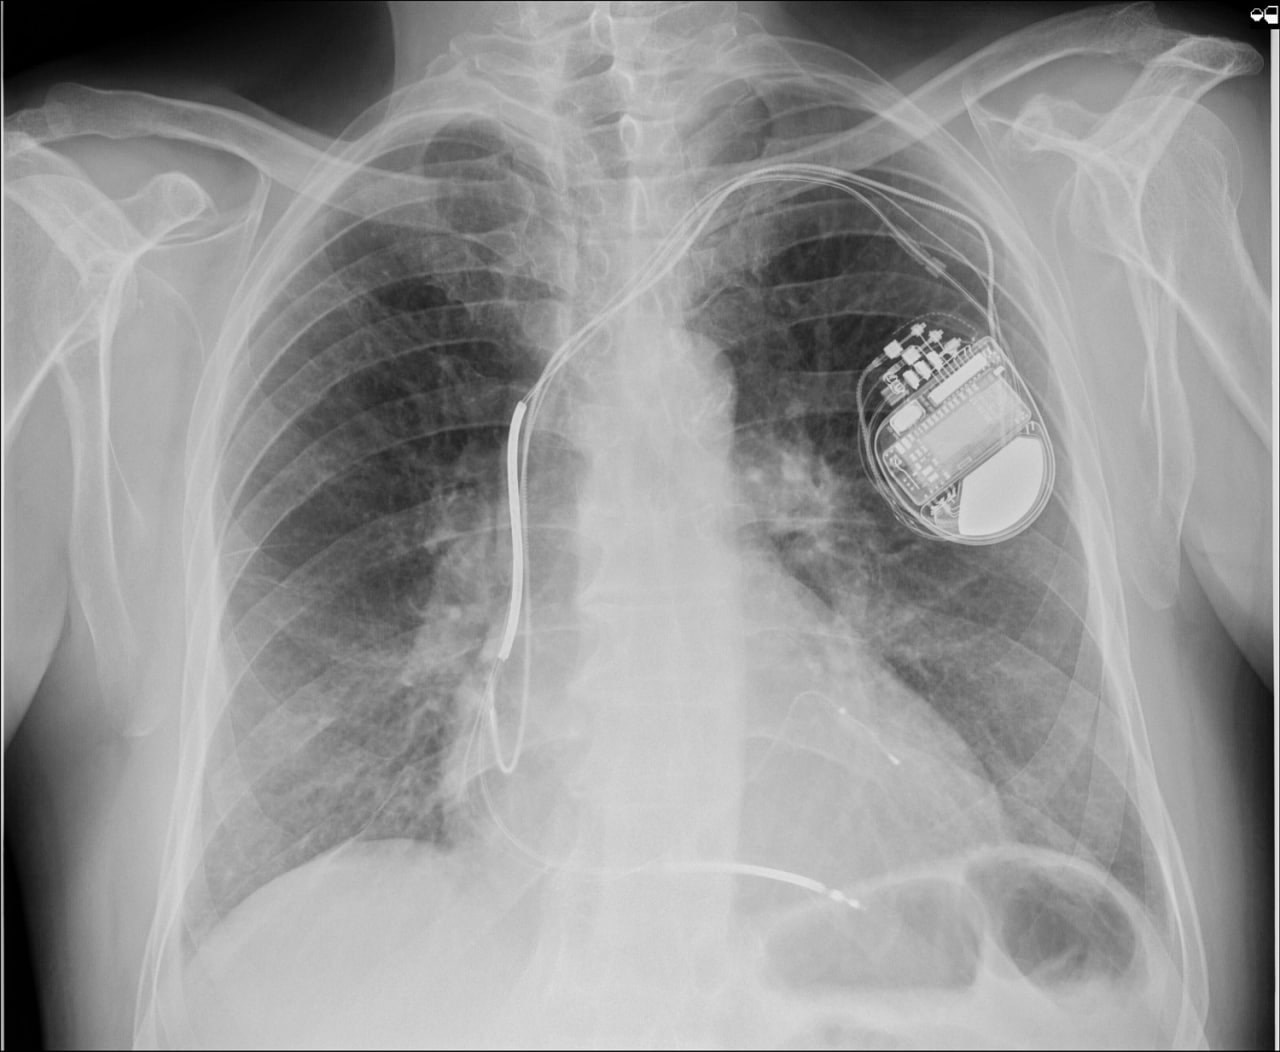

Очередному пациенту в ОККД имплантирован кардиовертер-дефибриллятор

На минувшей неделе в кардиохирургическом отделении №3 пациенту со сложной аритмией был имплантирован трёхкамерный кардиовертер-дефибриллятор. Вмешательство стало четвертым по счету, проведенным в стенах Областного кардиодиспансера менее чем за год. Впервые имплантация данного водителя ритма была проведена в ОККД 20 декабря 2023 года. Вмешательство выполнил заведующий КХО №3, к.м.н. Денис Сергеевич Терехов с командой врачей отделения.

«Имплантация кардиовертера-дефибриллятора с функцией ресинхронизирующей терапии требует тщательного подбора пациента, нуждающегося в данном устройстве, а также оценки потенциальной эффективности работы аппарата в каждом конкретном случае, при этом распространенность сердечной недостаточности в популяции не так уж мала. Ежегодно в Саратовской области выявляется от 30 до 50 человек, нуждающихся в операционной коррекции тяжелой сердечной недостаточности и желудочковых нарушений ритма с помощью многокамерных кардиовертеров-дефибрилляторов. До 2023 года в Саратовской области не было имплантировано ни одного такого устройства, но на сегодня мы успешно прооперировали уже четвертого пациента. Конечно, опыт пока небольшой, но на некоторых технических моментах внимание акцентировано. Надеемся на положительную перспективу развития этого направления аритмологии в нашем регионе и готовы набираться опыта, чтобы в дальнейшем максимально эффективно помогать бОльшему количеству пациентов», - отметил Денис Сергеевич.